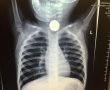

לראשונה בישראל: השתלת לב מלאכותי שהחליף לחלוטין את ליבו של החולה

חייו של מטופל בן 63 ניצל הודות להשתלת לב מלאכותי שלם שבוצעה השבוע לראשונה בארץ - בהדסה עין כרם, במבצע שהוביל צוות רפואי נרחב שכלל קרדיולוגים, כירורגי לב, מומחים בהרדמה וטיפול נמרץ, אחי חדר ניתוח וטכנאי מכונת לב ריאה.